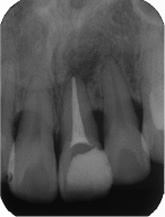

感染根管処置症例.1

主訴:2日前にかけたが、痛みやしみる症状はない。

- 被せ物を外し、過去に行った根管充填が不十分だった為、再度感染根管処置を行う。

- 1番細いファイルを使って、未治療の根の先まで到達したことを確認。

- ファイルを使って根っこの長さを測定・根管形成(根管-神経が入っていた管-を根管充填しやすい形に整えること)

- 根管充填剤が根尖(根っこの先端)まできっちりと充填されている。